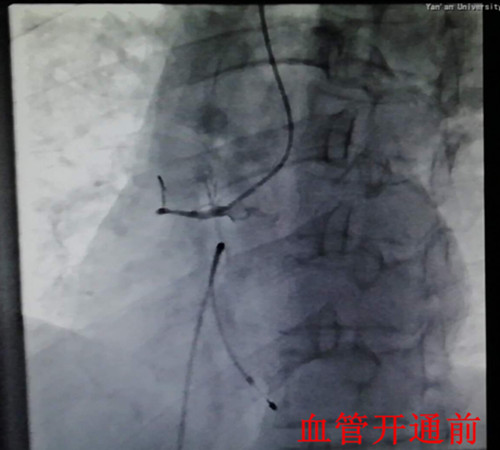

在一陣有效地?fù)尵戎?,患者在氣管插管、呼吸機(jī)輔助呼吸下,先行心臟臨時(shí)起搏器置入,后行左右冠狀動(dòng)脈造影,造影顯示:右冠狀動(dòng)脈呈鼠尾狀,開(kāi)口5mm處100%閉塞,旋支血管中遠(yuǎn)段60—99%彌漫狹窄病變。手術(shù)者立即開(kāi)通右冠狀動(dòng)脈,盡管患者在手術(shù)過(guò)程中不斷出現(xiàn)室速室顫,血壓下降,但隨著右冠狀動(dòng)脈遠(yuǎn)端血流恢復(fù),患者終于生命體征趨于平穩(wěn),安全返回監(jiān)護(hù)室繼續(xù)下一步治療。